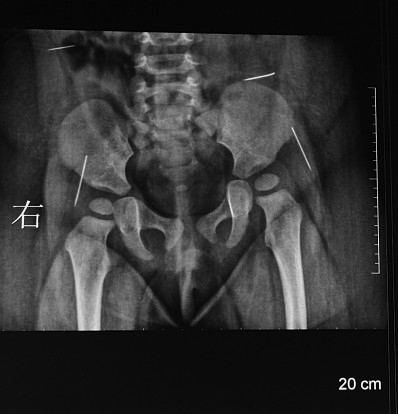

“有一点是肯定的,这四根缝衣针都是通过外力作用被戳进萌萌体内的”,陈卫兵告诉记者,从取出的缝衣针所附的体液颜色以及缝衣针所处体内位置的感染程度来看,这四根缝衣针在萌萌体内至少一个多月了。在萌萌手术前所拍的CT片上,清晰可见四个白亮亮长短不一的缝衣针,所处的位置分别在腰部和臀部两侧。陈卫兵告诉记者,臀部的两根缝衣针非常危险,已经移动到髋关节之间,有可能触及萌萌的坐骨神经,处于腰部的那根更危险,因为眼看着就要移动到肝脏位置。

昨天早晨8点30分,萌萌被推进手术室,到中午12点40分,医生将其体内四根没有针鼻的缝衣针全部取出。“整个手术可以说是惊心动魄,真的像大海捞针”,为萌萌主刀的陈卫兵向记者介绍,该手术要对萌萌进行全麻,但萌萌还小,最后选择用呼吸式麻醉对其全麻,骨科等科室的医生也被请到手术室一起为萌萌做手术,整个手术最难的还是要准确定位萌萌体内的四根缝衣针。在手术室里,他一边看着放射科所拍的X片,了解萌萌体内的缝衣针大概位置,一边用电话与放射科主任联系,通过早晨刚拍的CT片来准确定位缝衣针的位置。

在放射科,记者看到了萌萌手术前所拍的CT片,放射科主任鸥继华指着一张能看出缝衣针在萌萌体内一运动轨迹的片子告诉记者,这根缝衣针现在所处的位置已在接近臀部的髋关节,从运动轨迹来看,不排除是人为地从上往下戳进去的,而且取出的四根都没有针鼻,如果真的是人为的,那戳针的人还很有心计,因为如果不把针鼻去掉,那么整根缝衣针戳进皮肤后,由于针鼻有个小孔会造成缝衣针在进入萌萌体内时造成一定的阻力,缝衣针也就不会很快进入体内。四根缝衣针入体运动轨迹周围的软组织都已受感染。鸥主任告诉记者,他从事这么多年的放射工作,在一个人的体内,尤其是11个月大女婴的体内发现四根缝衣针还是头一次。